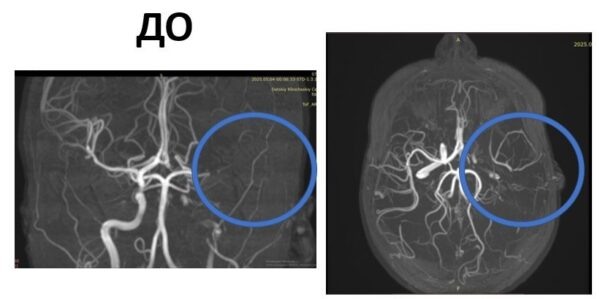

Фото: Детский центр им. Рошаля. vk.com

Чтобы исключить кровоизлияние в мозг, ребенку провели КТ, затем МРТ. Магнитно-резонансная терапия показала полную закупорку левой внутренней сонной артерии большим тромбом. Диагноз – обширный ишемический инсульт левого полушария мозга.